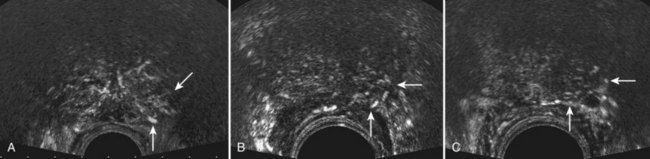

Using contrast-enhanced TRUS (CE-TRUS) for prospective prostate cancer detection, Halpern and associates (Halpern et al, 2001) demonstrated an increase in sensitivity from 38% to 65% versus baseline unenhanced imaging, without significantly altering specificity. Subsequent studies by our group and others have improved sonographic detection of malignant foci using CE-TRUS and targeted biopsy of enhancing lesions (Frauscher et al, 2001; Halpern et al, 2002a; Roy et al, 2003; Halpern et al, 2005; Heijmink and Barentsz, 2007). In a multi-institutional trial involving several European centers, CE-TRUS has been recommended for routine care in prostate biopsy (Wink et al, 2008). Imaging using microbubble contrast agents combined with three-dimensional image reconstruction of enhanced power Doppler images also demonstrated increased diagnostic accuracy (Unal et al, 2000) (Fig. 97–7).Gray-scale harmonic imaging is a relatively newer method for imaging ultrasound contrast agents that provides better spatial and temporal resolution compared with color Doppler imaging. A variation on gray-scale harmonic imaging, flash-replenishment imaging, provides improved visualization of neovessels that are below the standard resolution of even gray-scale ultrasonography. Flash-replenishment imaging uses a combination of high-power flash pulses to destroy contrast microbubbles, followed by low- power pulses to demonstrate contrast replenishment. A composite image is constructed depicting the vascular architecture through maximum intensity capture of temporal data in consecutive low-power images, and it can be used for real-time targeted transrectal biopsy of areas of increased or abnormal vascularity. Using this technique, we have demonstrated much finer vascular detail for targeting biopsy, and targeted biopsy cores were significantly more likely to be cancerous than random systematic biopsy cores (Linden et al, 2007) (Fig. 97–8). Future developments in these and other imaging modalities that can selectively visualize prostate cancers based on the presence of angioneogenesis may ultimately allow more accurate localization of the sites of cancer.

Figure 97–7 Unenhanced color (A) transrectal ultrasonography (TRUS) and power Doppler (B) TRUS fail to detect evidence of an underlying malignancy. After infusion of a microbubble contrast agent, color (C) TRUS and power Doppler (D) TRUS demonstrate an area of increased flow in the left midgland that proved to be a Gleason 3 + 4 = 7 adenocarcinoma on targeted biopsy (arrows).